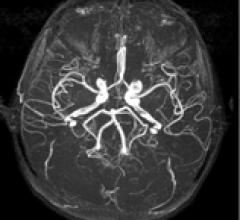

October 14, 2010 – An injectable magnetic resonance angiography (MRA) blood pool imaging agent has been released in Canada. Ablavar, which is made by Lantheus Medical Imaging and previously marketed as Vasovist, is indicated for contrast-enhanced MRA for visualization of abdominal or limb vessels in patients with suspected or known vascular disease.